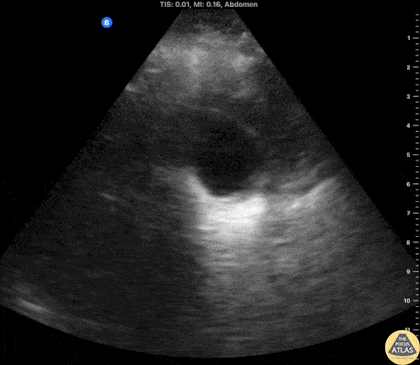

Biliary - Impacted Gallbladder Neck Stone

20s F presented with recurrent postprandial RUQ pain. POCUS demonstrated multiple hyperechoic stones in the gallbladder including one in the gallbladder neck. No pericholecystic fluid or wall thickening were noted, and the common bile duct was normal caliber. Formal RUQ US confirmed these findings, and the patient was taken to the OR by the surgery team for cholecystectomy. Dr. Nhu-Nguyen Le, Ultrasound Fellow Denver Health Ultrasound Fellowship